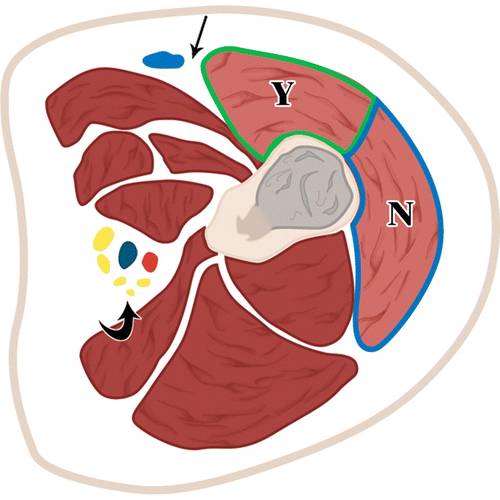

11 -小腿的插图。

轴位图显示胫骨活检(绿色和箭头)的最佳入口位置,避免肌肉室。T =胫骨,F =腓骨。